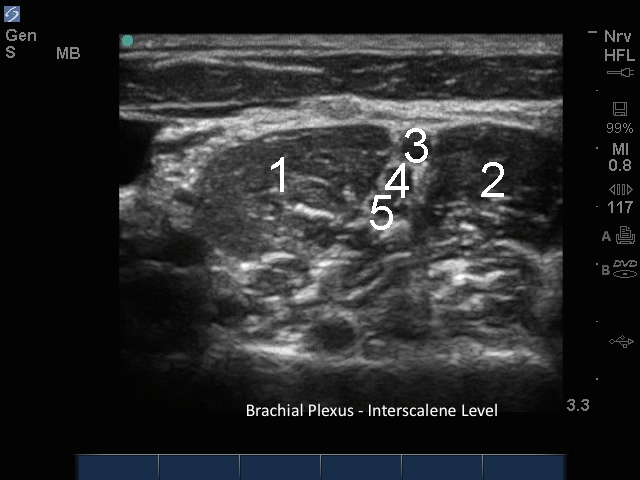

M-Turbo:腕神経叢斜角筋間レベル3

ASM

MSM

C5

C6

C7